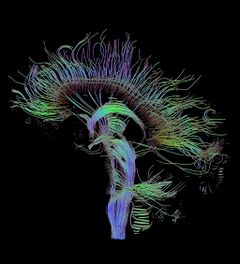

الكونكتوم connectome ( []kəˈnɛktoʊm[])، هي خريطة شاملة للوصلات العصبية في المخ، ويمكن النظر فيها "كمخطط تشبيك" لها. بشكل أكثر شمولاً، تشمل الكونكتوم رسم خريطة لجميع الوصلات العصبية في الجهاز العصبي للعضيات.

إنتاج ودراسة خرائط الكونكتوم، المعروفة بالكونكتومية، يمكن ترتيبها في مقياس من الخريطة المفصلة لجموعة العصبونات والتشابكات العصبية في الجهاز العصبي للعضيات أو جزء منه لوصف واسع النطاق للربط الوظيفي والهيكلي بين جميع مناطق البنى القشرية وتحت القشرية. يستخدم مصطلح "الكونكتوم" بصفة رئيسية في الجهود العلمية لتصوير، رسم خريطة، وفهم تنظيم التداخلات العصبية في المخ.

الهدف النهائي للكونكتومات هو رسم خريطة للمخ البشري. يتم هذا الجهد من خلال مشروع الكونكتوم البشرية، برعاية المعاهد الوطنية للصحة، الذي يركز على بناء خريطة شبكية للمخ البشري لدى البالغين الأصحاء.